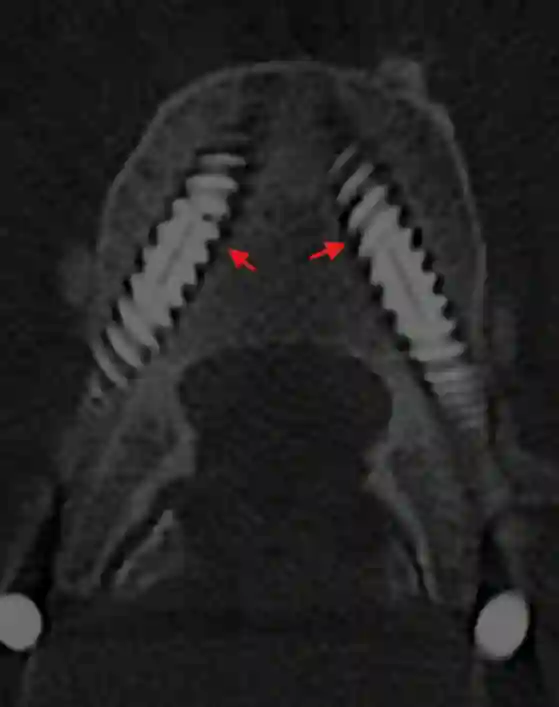

Seit einigen Jahren sind Karbonpedikelschrauben verfügbar. Pedikelschrauben aus Karbon haben den Vorteil, dass diese weniger Artefakte in der MRT Bildgebung verursachen[^3]. Dies ist insbesondere für Patienten mit Tumorleiden an der Wirbelsäule von Vorteil, um eine optimale Nachbehandlung zu planen.

Herkömmliche Pedikelschrauben verursachen in der MRT Bildgebung Artefakte, sodass die MRT Bildgebung als suboptimal zur Beurteilung von Pedikelschrauben gilt. Der Goldstandard zur Lagebeurteilung von Pedikelschrauben ist die CT-Bildgebung.